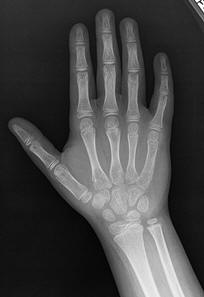

Normal hand RA - Damaged finger joints RA - Fused finger joint

Normal hand bones RA - Damaged hand bones RA - Damaged hand

Description           English: Projectional radiography ("X-ray") of a normal hand of a 8 year

old male, by dorsoplantar view.